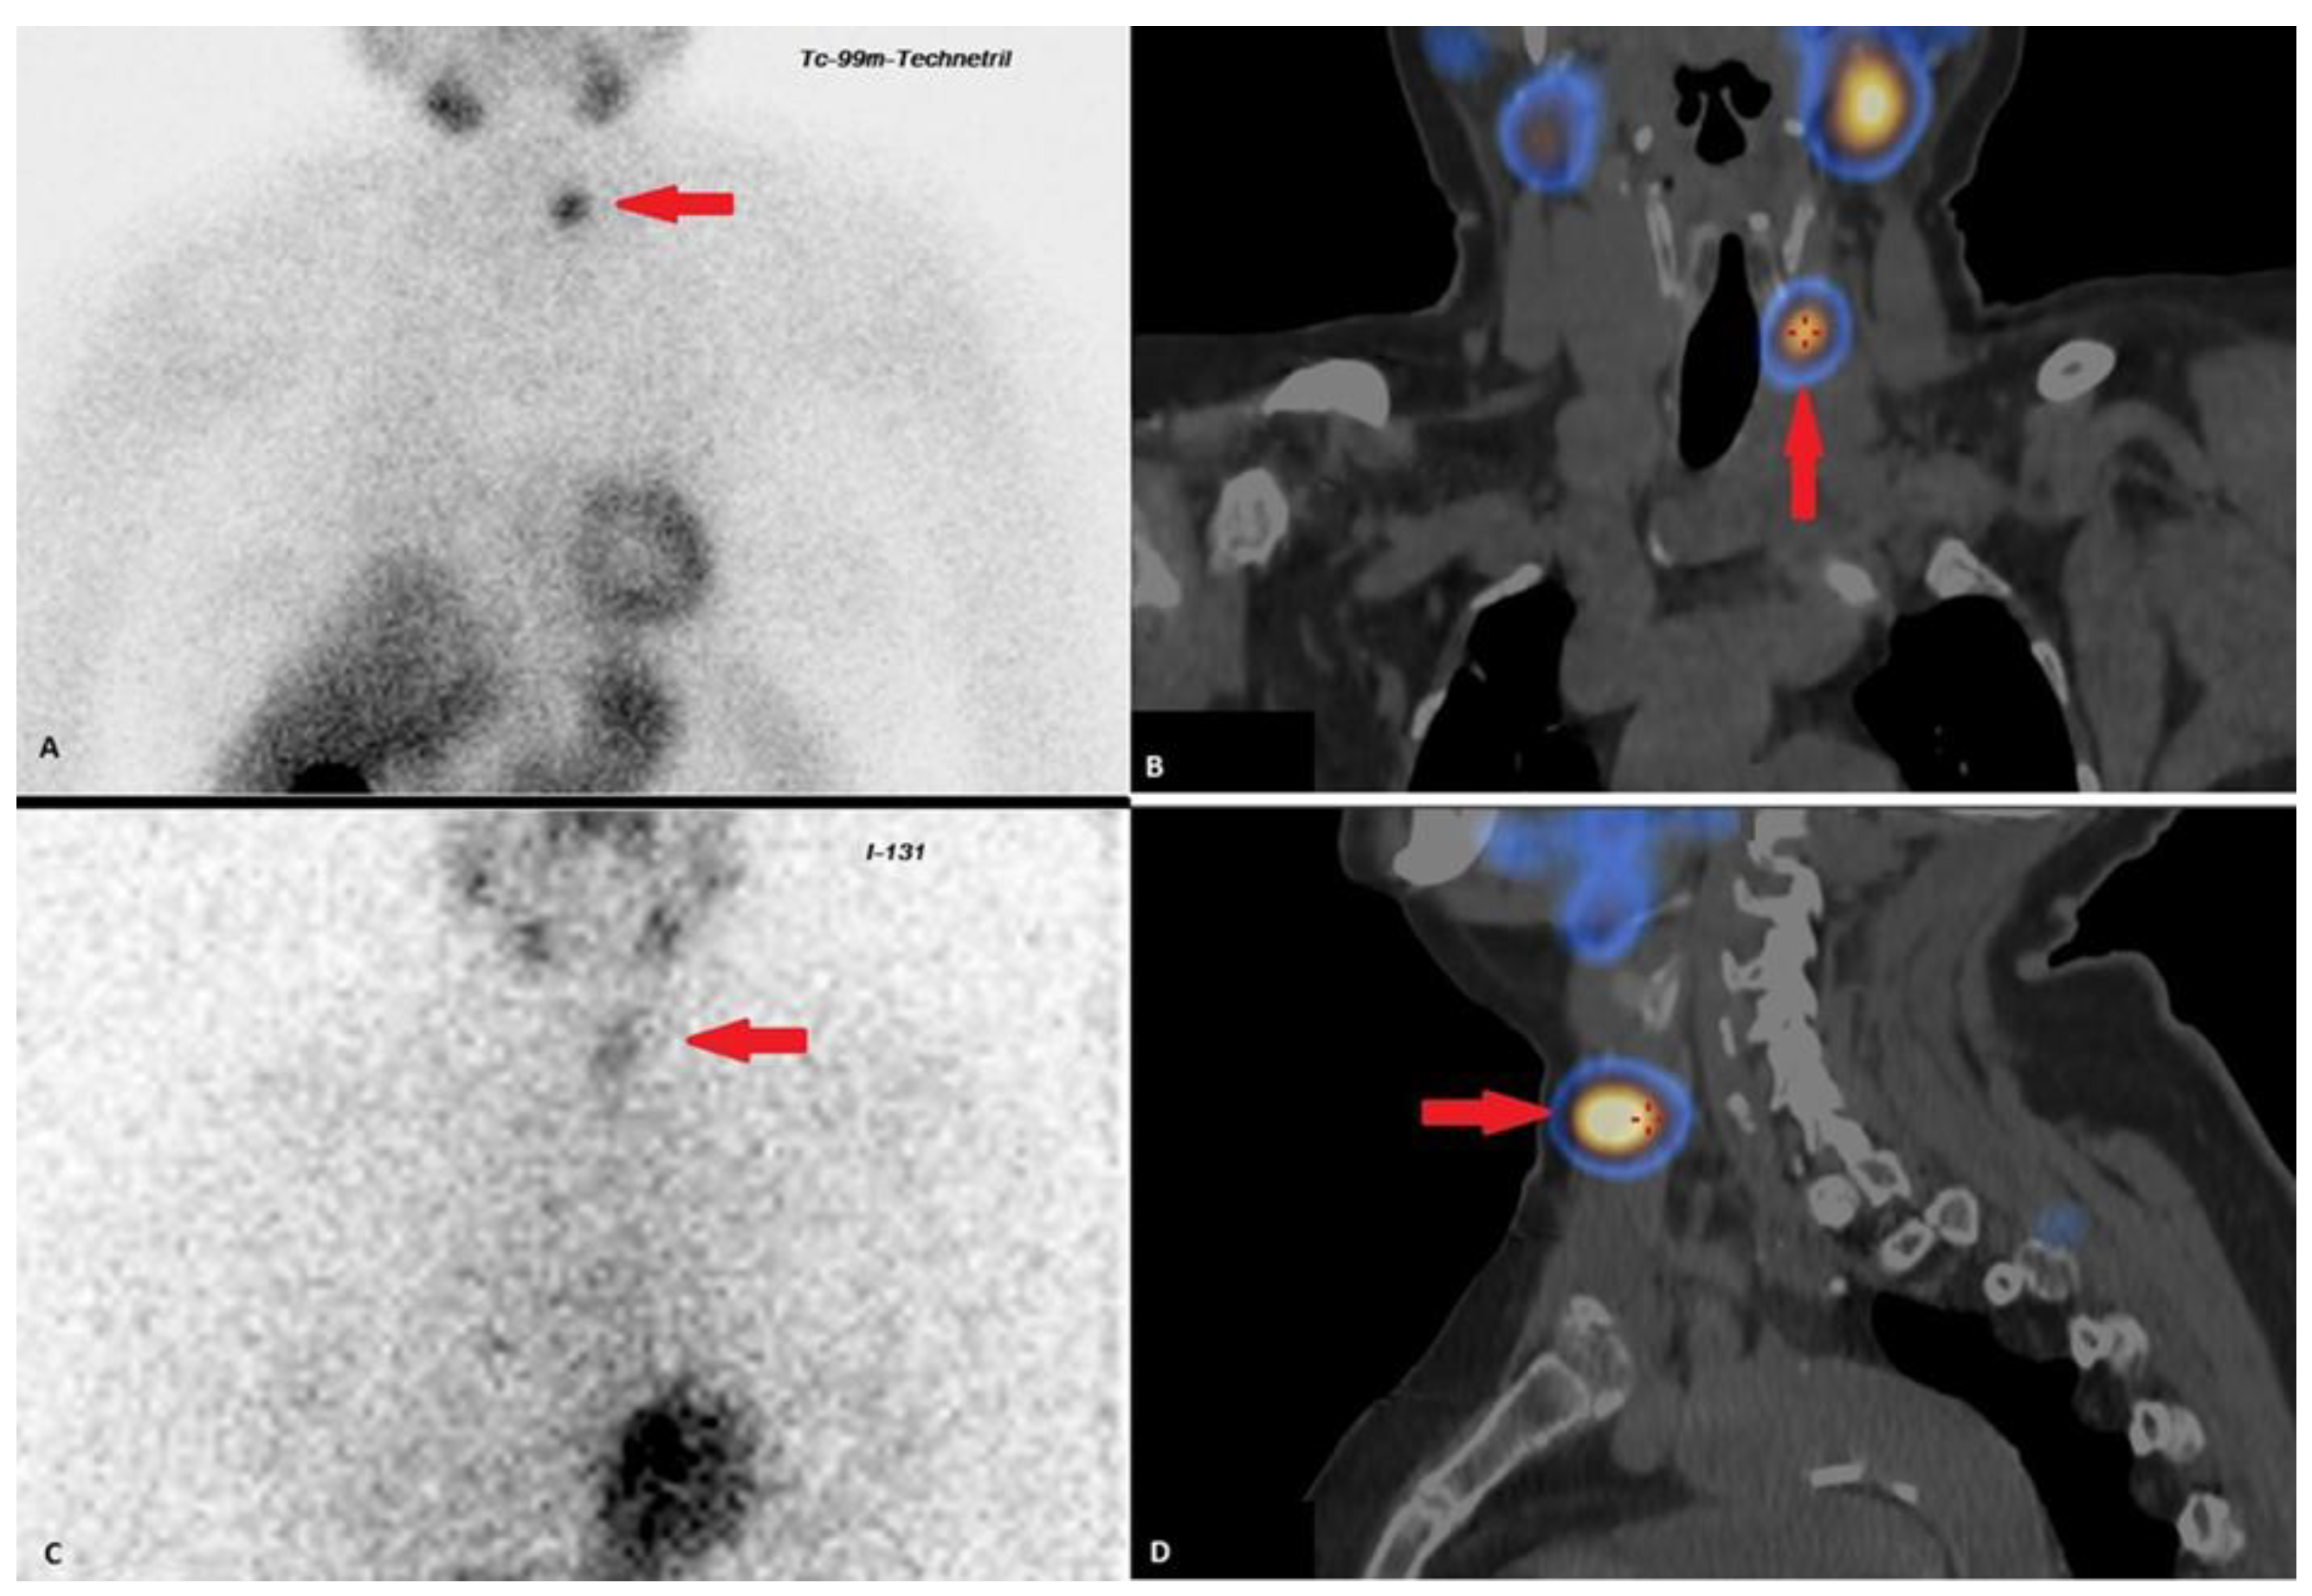

| 2018–2019 | Ultrasound: ‘multiple hypoechoic lesions with dimensions of 12 × 7 mm, 9 × 6 mm, 11 × 6 mm and 9 × 5 mm of the left lobe; 1.4 cm lower a new lesion 0.6 cm in diameter’ 99mTc-MIBI scintigraphy with SPECT/CT: ‘a round lesion with clear contours and an inhomogeneous structure, measuring 14 × 10 × 15 mm and with significant radiopharmaceutical uptake, above the jugular notch, anteriorly to the trachea, slightly to the left of the midline’. Planar whole-body scintigraphy with I-131: tissue accumulating 131I is visualized in the projection of the thyroid bed, on the left. | Surgery 3—total parathyroidectomy with the adjacent soft tissues and central lymph node dissection using intraoperative navigation methods | Metastases of parathyroid cancer (with a diameter of about 15 mm) and papillary thyroid cancer (follicular variant) to the lymph nodes with total and subtotal replacement of node tissue IHC: diffuse expression of PTH and parafibromin (Figure 1B,C), Ki-67—7%. |